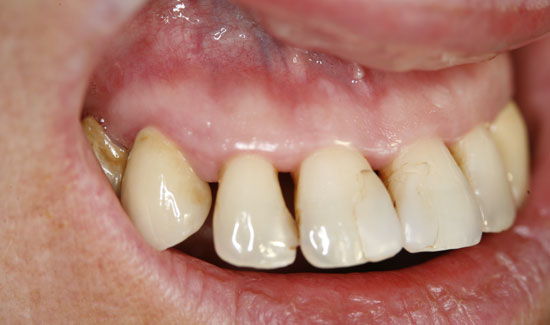

Fig. 3: Condition after ozone therapy. Chlorhexidine staining of the teeth